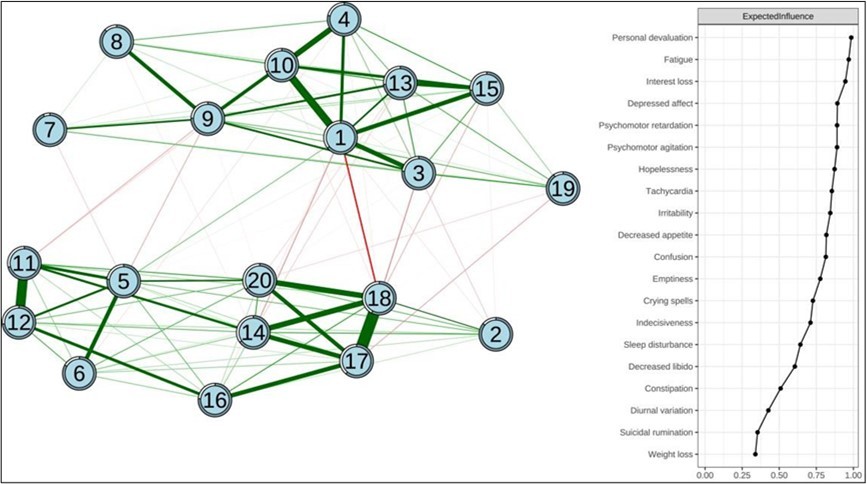

The structure of the depressive symptom network for teachers is depicted in the left side of Figure 1. Of the 190 edges, 110 (57.89%) were positive, demonstrating interconnectedness among the depression symptoms. The strongest connection was observed between “Sense of Futility” and “Emptiness of Life”, followed by the connections “Difficulty in Thinking - Decreased Ability” and “Depressed Affect - Fatigue Easily”. Additionally, node predictability values varied from 57.6% to 93.4%, with an average of 75.0%. This suggests that, on average, 75.0% of the variance in the network nodes could be accounted for by their adjacent nodes. Notably, “Weight Loss” and “Sense of Worthlessness” exhibited the highest predictability within the model, whereas “Emptiness of Life” displayed the lowest predictability.

Figure 1.Network structure of depressive symptoms in teachers and expected influence (z-score) of each variable

The significance of each node within the network is detailed in the right side of Figure 1. The most central symptoms of teacher depression identified were “Sense of futility” (EI = 0.986), “Fatigue” EI = 0.969), “Interest loss” (EI = 0.946), and “Depressed affect” (EI = 0.892). The depression network demonstrated good stability. The CS-C of EI was 0.75, indicating that the EI after discarding 75% of the data was still significantly correlated with the original data at the 95% confidence level (Figure 2). Further information on the edge weight confidence intervals (CI) and differences in node strength for each network can be found in the supplementary materials (Figure S1-S2).

Figure 2.The stability of network structure by case dropping subset bootstrap